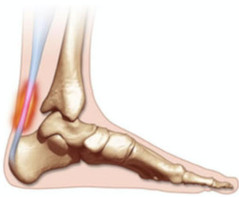

A tendinite de Aquiles é aquela dor chata que aparece na parte de trás do seu calcanhar, bem ali onde o músculo da panturrilha se liga ao osso do pé. Sabe, é uma inflamação desse tendão forte que usamos para correr, pular e até para andar. Quando exigimos demais dele, ou quando ele já está cansado e fraco, o problema aparece.

A dor na parte de trás do calcanhar, que piora com o movimento e pode apresentar inchaço, é um forte indicativo. Se a dor persistir, procure um médico para ter o diagnóstico correto.